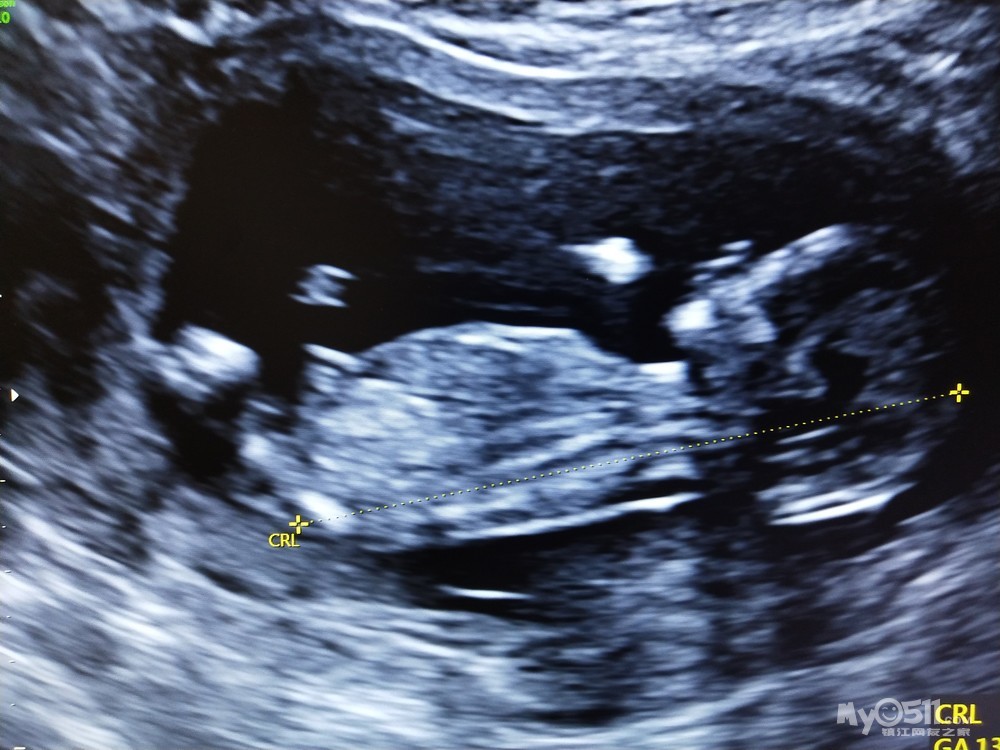

这个宝宝是我的试管宝宝,打了无数的针,吃了很多的药,终于移植成功,现在终于15周了。